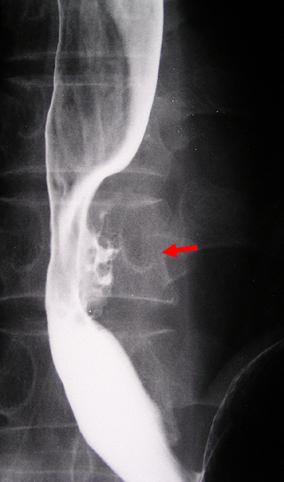

질환(병리주체)의 분류 악성 상피성종양/편평상피암

부위(장기별) 식도/하

검사방법 X-P

종양의 육안분류 3형(궤양침윤형)/

종양의 최대경(밀리미터) 35~40

종양의 심달도 s(a)